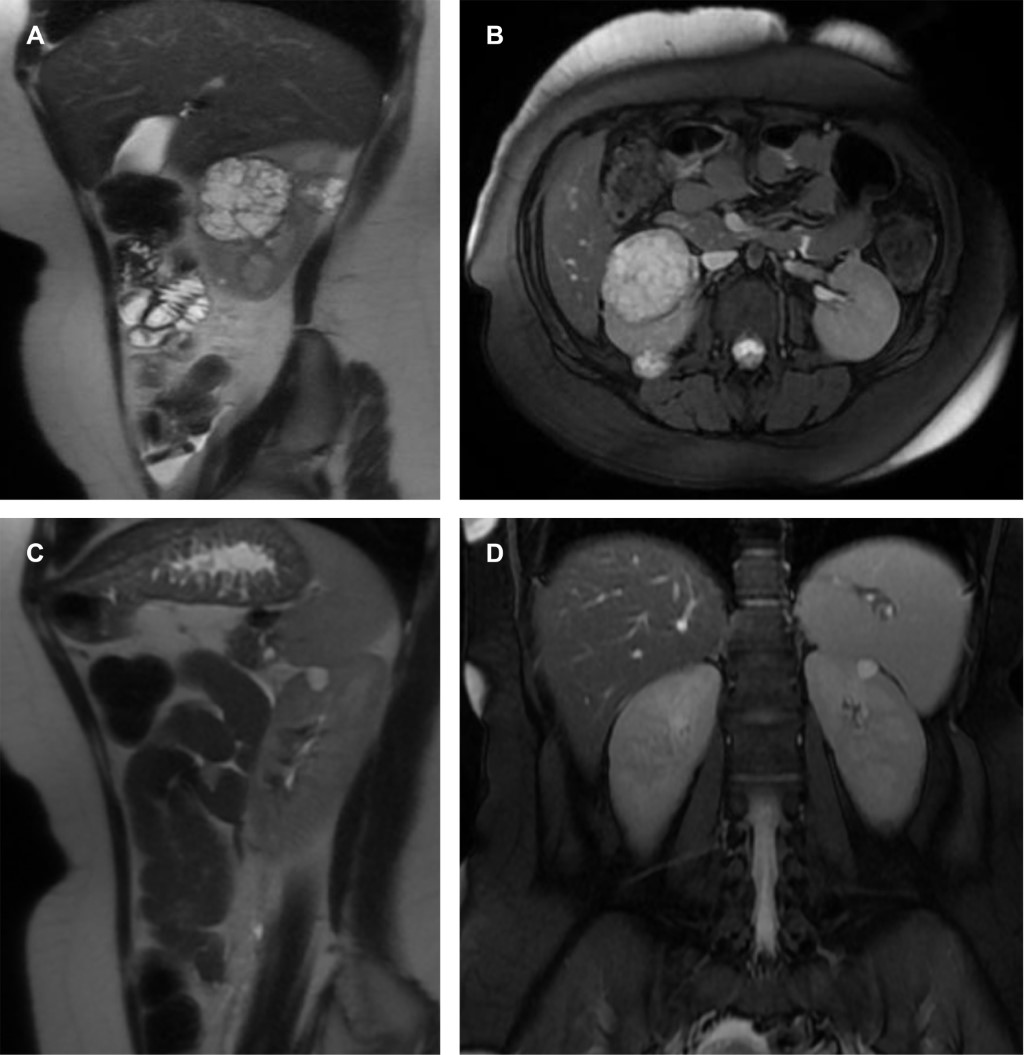

Mujer de 23 años con diagnóstico reciente de enfermedad de VHL y evidencia de hemangioblastoma en cerebelo que requirió tratamiento quirúrgico, acude asintomática para realización de RM abdominal como parte de sus estudios de tamizaje, en donde se evidenciaron quistes complejos en ambos riñones (Figura 1) y en páncreas (Figura 2).

Figura 2